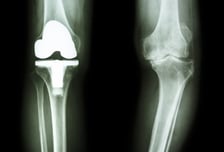

진통제 먹다 결국엔 인공관절? 달라진 무릎 관절염 치료, '이때'가 중요해

매년 4월 28일은 대한정형외과학회가 제정한 '관절염의 날'이다. 관절염은 연골의 손상이나 퇴행성 변화 등으로 관절에 염증이 생겨 통증과 기능장애가 발생하는 질환이다. 뼈와 뼈 사이에서 '쿠션' 역할을 하는 연골이 손상돼 발병한다. 나이, 가족력, 비만, 관절의 외상, 염증 등 원인이 다양하다. 꼭 나이가 들면서 생기는 질환은 아니다. 어려서부터 관절에 병을 앓았다면 비교적 젊은 나이에도 관절염이 발생할 수 있다. 관절염의 '대명사'는 무릎 관절염이다. 무릎은 우리 몸에서 신체의 하중을 지탱하는 가장 큰 관절로 평상시 사용량이 많아 관절염에도 취약하다. 국민건강보험공단이 2018년~2022년 환자를 분석해보니 무릎 관절증 진료인원은 2018년 287만 4000여명에서 2022년 306만 6000여명으로 19만 1424명(6.7%) 증가했다. 남성은 2018년 86만 101명 대비 12.4% 증가해 2022년 96만 6965명이 진료했다. 여성은 2022년 209만 8638명으로 2